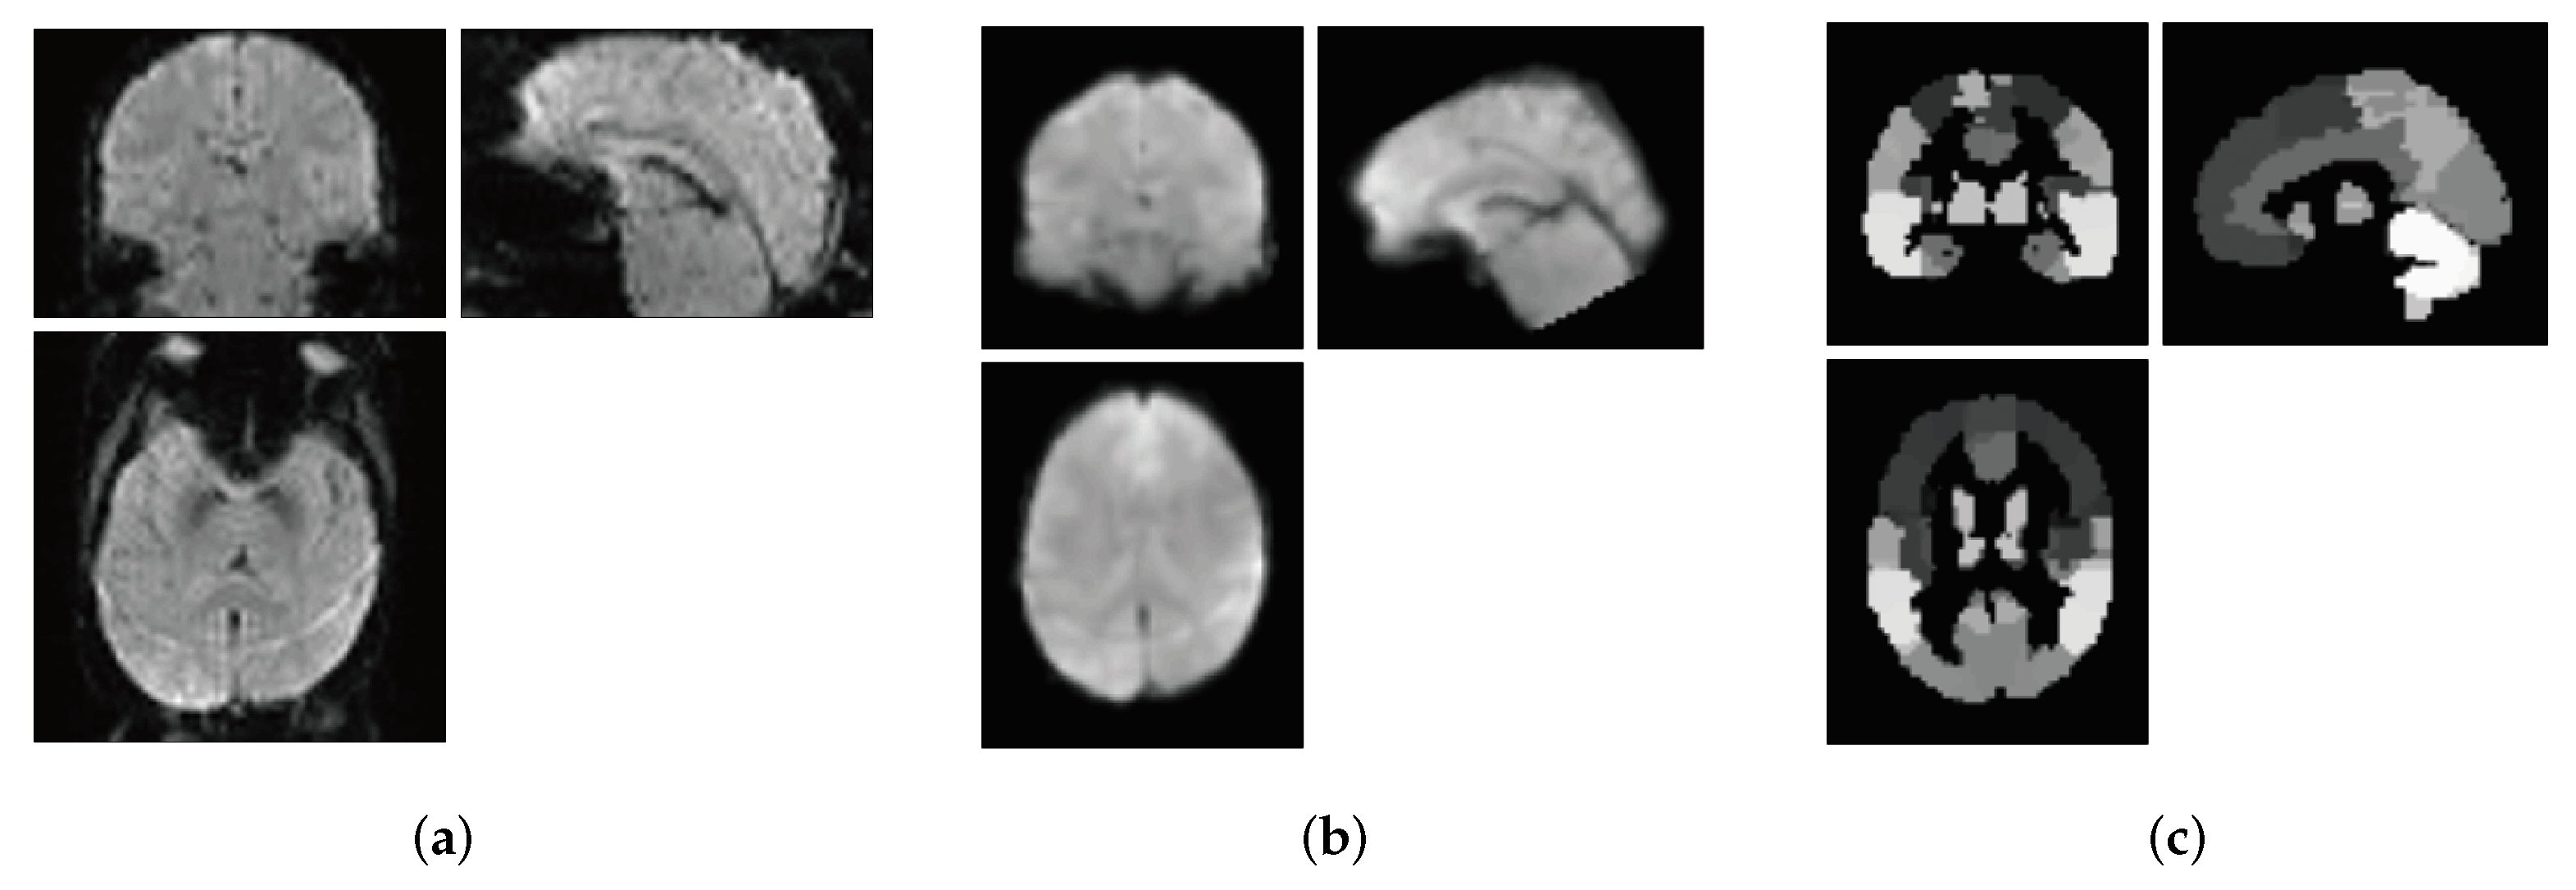

2.2. Data Preprocessing

5.1. Effect of Brain Regions